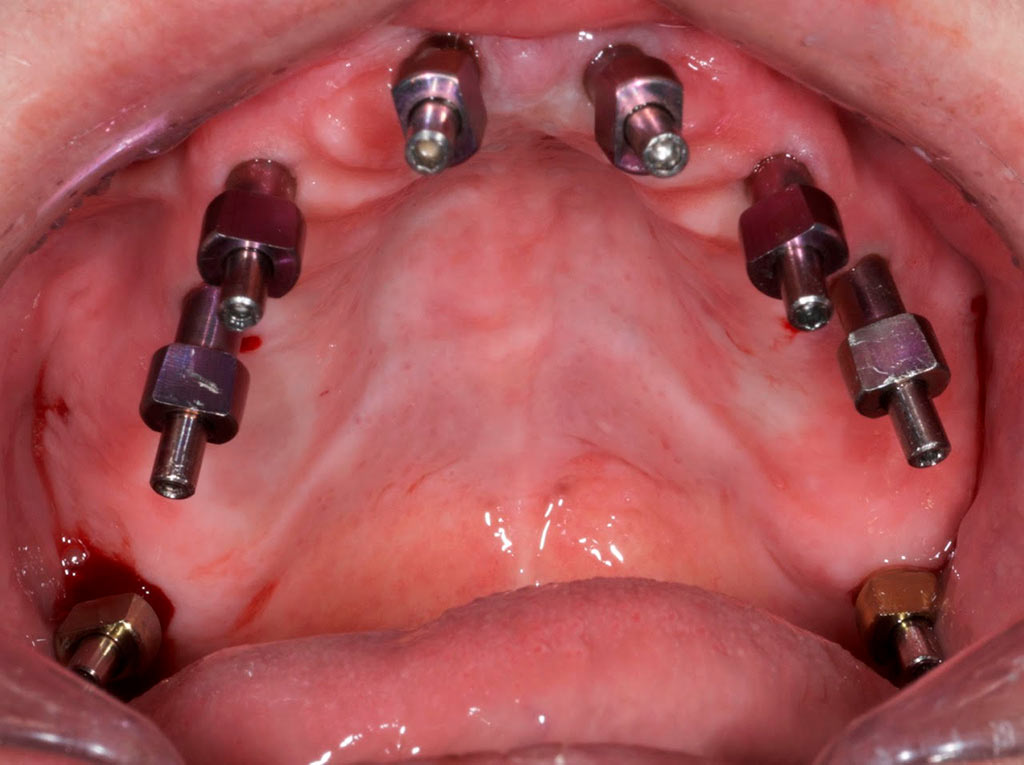

Completa inmediata,cirugía guiada, prótesis, puente de zirconio

Rehabilitacion de paciente con destrucción dental